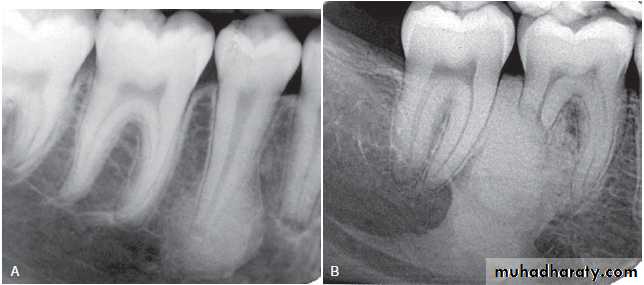

Osteoradionecrosis of the maxilla. (A) before radiotherapy and (B) within 6 months of receiving the radiation. Note the combination of bone sclerosis, bone destruction around the teeth and alveolar crest and widening of the periodontal membrane space.

B

A

( A and B ) of the same patient taken 7 years apart reveal thickening of the lamina dura around the teeth.

( A and B ) of the same patient taken 1 year apart demonstrate a developing sclerotic bone pattern with a sequestra (arrow) related to bisphosphonate therapy.